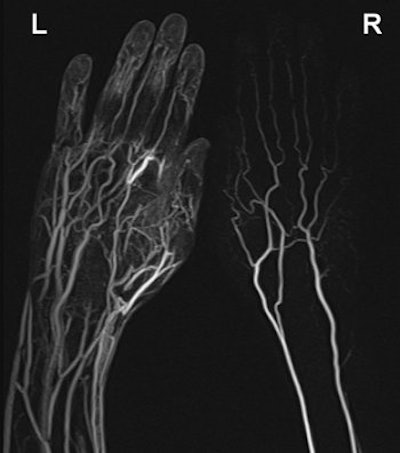

![]() |

| Maximum intensity projection from reconstructed 3D contrast-enhanced MR angiography of both hands of 25-year-old healthy male volunteer after IV administration of gadobutrol using a flow rate of 0.5 mL/sec. Imaging sequence was obtained 40 seconds after initiation of contrast injection. Subsystolic cuff compression is applied to upper arm on right side. Major venous contamination (venous contamination score = 2) is observed on noncompressed left side. Gluecker TM, Bongartz B, Ledermann HP, Bilecen D. "MR Angiography of the Hand with Subsystolic Cuff-Compression Optimization of Injection Parameters" (AJR 2006; 187:905-910). |

Upper arm compression was applied unilaterally with a standard blood pressure cuff during all three studies. "Subsystolic compression was performed with a pressure value of 30% less than the brachial artery systolic blood pressure measured by the examination," the authors explained. The volunteers received 0.1 mg/kg dose of gadobutrol followed by a saline flush for each 140-second-long study.

All 10 subjects completed the exams and tolerated the cuff compression, the authors stated in their results. For all three flow rates, a contrast-to-noise ratio (CNR) of more than 10 was obtained. In the venous vessels, the least venous contamination was measured with a flow rate of 0.5 mL/sec.

On qualitative analysis, this latter flow rate starting at 60 seconds was given the highest score by the reviewers. Conversely, studies performed with an injection rate of 1.5 mL/sec received the worst score for venous contamination.

Diminished venous contamination was seen on the compressed side for all flow rates, the group reported. Again on qualitative analysis, both reviews saw less venous contamination on the compressed side and with a flow rate of 0.5 mL/sec.

The authors acknowledged that their sample size was small and that the results may differ in patients with problematic hands, such as vasospasm, vascular stenosis, or trauma. Still, these results are promising, they noted. They also recommended that reducing the applied pressure to 50% less than the brachial artery systolic blood pressure for even better results.